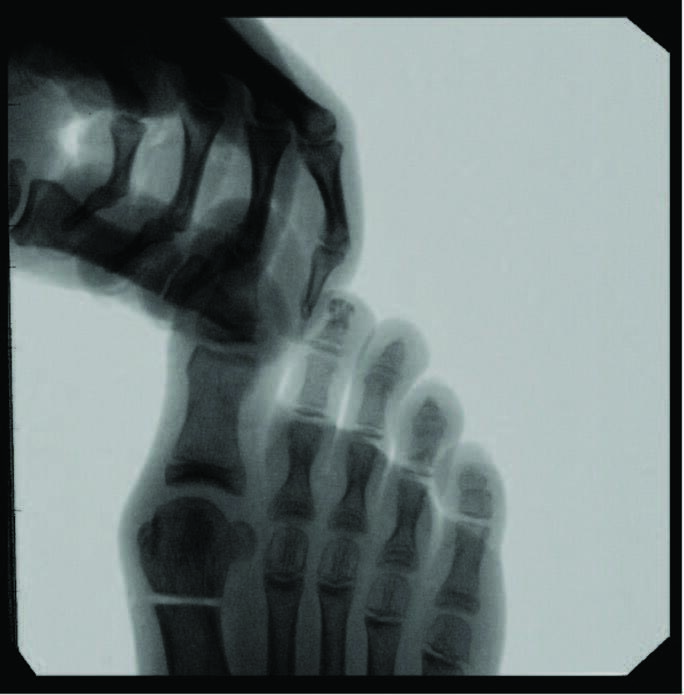

Minimally Invasive Approaches To Juvenile Hallux Abducto Valgus Deformity

A sequential examination from hindfoot to forefoot is crucial to assess the stability of the triplanar deformity and contributing etiology. Evaluating the suppleness of the subtalar joint and Achilles tendon clinically, through range of motion, and radiographically, by measuring the talocalcaneal angle and amount of calcaneal positioning in the frontal plane, is an important first step. In Root’s theory of subtalar joint neutral, pes valgus leads to a progressive inversion of the first metatarsal relative to the hallux during the propulsive period of the stance phase in gait.3 This forefoot instability progresses MTPJ joint subluxation with the hallux tracking laterally. Forefoot evaluation includes assessing the dorsal and plantar deviation of the first tarsometatarsal joint and the flexibility of the first metatarsal joint and hallux deviation, all while the subtalar joint is in neutral.3

Predictors of juvenile HAV severity, in addition to subtalar joint pronation, include: rounding of the first metatarsal head; an atavistic cuneiform; a hypermobile or long first ray; and a high metatarsus primus adductus angle.4 Additional pes planus-related radiographic measurements include an increased first intermetatarsal angle, reported in 26.6 percent of adolescents and an increased metatarsus primus varus angle in 8.1 percent.5 Anatomic abnormalities such as Achilles equinus contractures, digital contractures, syndactyly, metatarsus adductus, hereditary exostoses, and congenital hip dislocation may need attention for long-term successful HAV treatment. Other considerations include brachymetatarsia, where a shortened lesser metatarsal leads to an abnormal transverse metatarsal parabola, allowing more lateral deviation of the hallux and increased metatarsus varus angle due to soft tissue balancing effects.

When we approach surgical correction of hallux valgus, goals include realigning the hallux joint across all three planes, improving the first intermetatarsal angle, restoring and maintaining a pain-free joint, improving cosmesis, and allowing a return to comfortable shoes. Inclusion criteria for surgery that we consider include intact vasculature, Vitamin D-25 levels above 40 nmol/dl, and medical stability in the presence of comorbidities. Percutaneous hallux valgus correction has indication for spastic or non-spastic bunions, revisions, and a wide range of intermetarsal angles. Other exclusion considerations include patients with severe osteoarthritis or osteomyelitis near the first metatarsophalangeal joint.